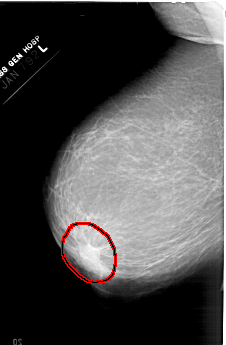

A_1380_1.LEFT_CC

FILE: A_1380_1.LEFT_CC.OVERLAY

TOTAL_ABNORMALITIES 1

ABNORMALITY 1

LESION_TYPE MASS SHAPE IRREGULAR MARGINS ILL_DEFINED

ASSESSMENT 4

SUBTLETY 5

PATHOLOGY BENIGN

TOTAL_OUTLINES 1

BOUNDARY